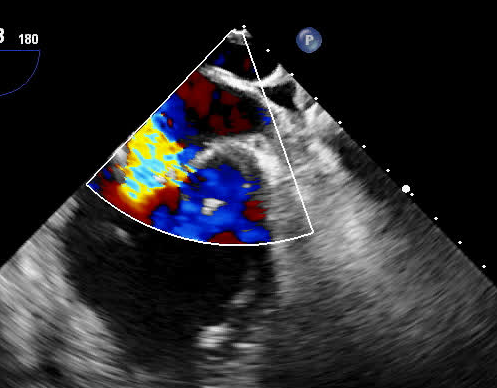

术前二尖瓣大量反流

77岁的彭奶奶经心脏彩超显示二尖瓣大量反流,心脏明显增大,因为呼吸困难辗转多家捷克论坛 就诊,经过抗心衰药物规范治疗后仍不能缓解症状。以往该类患者有两种治疗方式:一是实施传统外科换瓣手术,二是药物保守治疗。但对于高龄、集多种老年疾病于一身的患者,实施外科手术需要开胸并在体外循环下进行,风险极高;药物治疗仅能改善其心衰症状,但治标不治本,会导致心衰反复发作。

术前,科室组织多学科会诊,由心脏大血管外科、心内科、麻醉科等多位专家共同讨论并一致认为,老人二尖瓣病变严重,同时合并有冠心病、心律失常、心功能不全等多种高危因素,已不适用外科手术,在微创下不开胸实施二尖瓣钳夹术是最佳选择。经手术团队充分缜密的术前准备,在超声引导下器械经股静脉穿刺房间隔,将MitraClip系统送入患者左心房,到达二尖瓣反流处,在经食道超声及DSA引导下,术者通过评估二尖瓣反流位置、抓捕位置、反流程度,精准夹合,成功植入2个二尖瓣夹。二尖瓣从术前的大量反流减轻到微量反流,肺静脉的逆流完全消失,血压从偏低恢复到正常状态,第二天即下床,术后第5天顺利出院。